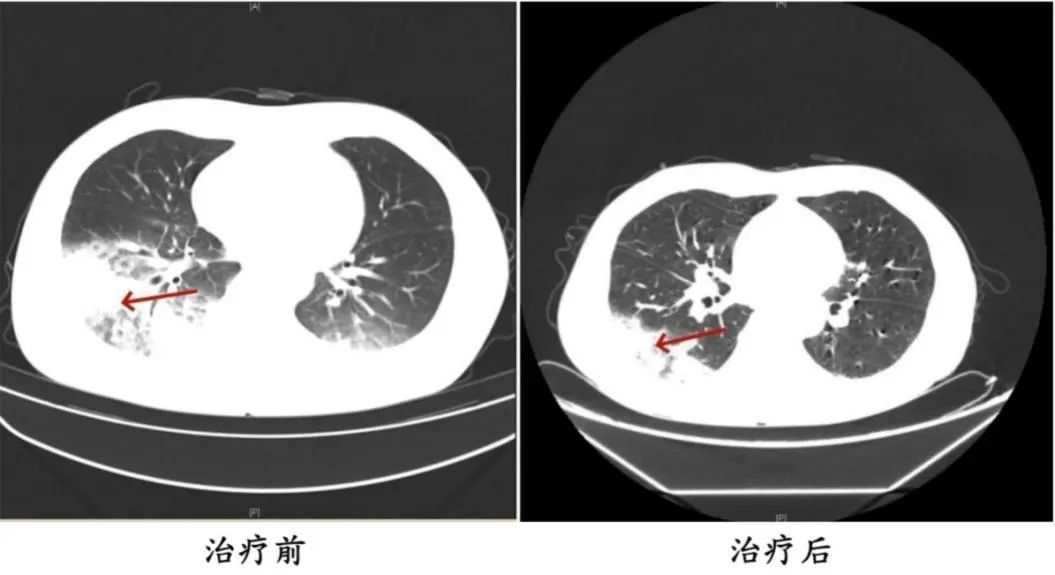

李先生肺部治疗前与治疗后的对比

据报道,李先生开了3天空调后,出现了肌肉酸痛、头痛、发热和咳嗽等症状。起初,他以为是吹空调吹感冒了,于是自行服用感冒药,但病情并未好转,反而愈发严重。家人见状,立即将他送往成都市第五人民医院感染性疾病科。胸部CT显示李先生的左肺已出现大面积白色影像,几乎占据一半肺部。经过肺泡灌洗NGS检测,最终确认“罪魁祸首”是嗜肺军团菌。